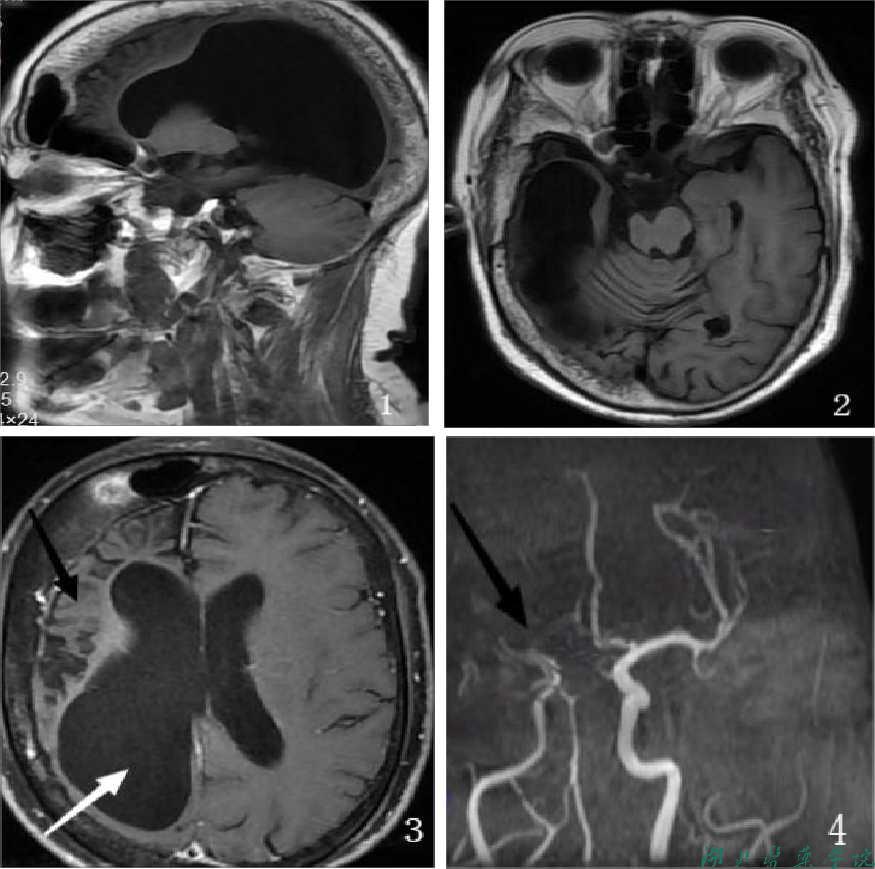

影像报告【知识点2:Dyke-Davidoff-Masson综合征的影像学特征】:(附原始MRI图像,图1、2、3、4)

| 磁共振平扫+增强

右侧大脑半球皮层及皮层下脑实质体积缩小,右侧残余脑白质T2t1a1信号增高,右侧大脑半球脑沟、裂增宽,右侧脑室明显较对侧扩大,中线结构稍向右侧偏移。右侧额颞顶枕骨板障明显增厚。右侧额窦较对侧明显扩大,其内气化良好。左侧放射冠区见多发斑点状异常信号,T2WI及T2f1a1r是高信号,左枕叶(侧脑室后角下)见一囊状T2WI高信号影,直径约0.9cm。颅内未见明显流空信号团注G-DTPA增强扫描:颅内未见明显导常强化灶。

1.戴克-戴维多夫-马森(Dyke-Davidoff-Masson)综合征可能性大。

2.左侧放射冠区多发腔梗。

3.左侧枕叶囊肿。

| 磁共振血管成像

右侧大脑中动脉M1段纤细,远端分支未见显影;左侧大脑后动脉P2段及右侧大脑前动脉A2、A3段中重度狭窄;颅内未见明显异常血管显示。

1.右侧大脑中动脉M1段纤细、重度狭窄、闭塞;左侧大脑后动脉P2段及右侧大脑前动脉A2、A3段中重度狭窄。

2.双侧胚胎型大脑后动脉。

1. Dyke-Davidoff-Masson综合征( Dyke-Davidof-Masson syndrome,DDMS)是一种罕见的中枢神经系统疾病,是脑偏侧萎缩的常见病因临床以反复癫发作、面部不对称、一侧肢体偏瘫、智力发育低下及精神异常等为特征。典型影像学表现为单侧大脑半球萎缩、同侧侧脑室扩张、部分脑实质有较大的软化灶、同侧颅骨增生、鼻窦及乳突窦增大等。由Dyke、Davidoff和Masson于1933年首先报道。

2. 临床进程是不对称的大脑半球增长发育,伴有一侧萎缩负占位效应。脑实质容量的减低导致了同侧侧脑室和脑沟扩大。这种适应性改变,其结果导致同侧颅盖骨增厚、以及鼻旁窦增大。

3. 大脑镰移位是DDMS的一种关键性改变

典型影像学表现为:单侧大脑半球萎缩、同侧侧脑室扩张、部分脑实质有较大的软化灶同侧颅骨增生、鼻窦及乳突窦增大等。